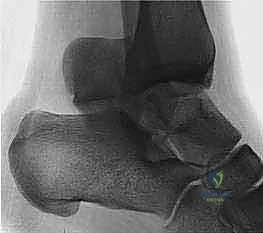

The type I fracture is nondisplaced. Disruption of blood flow is limited to the anterolateral region of the bone. I recommend a computed tomography (CT) scan to confirm no displacement of the fracture before diagnosing a type I fracture. Historically, Hawkins reported a 13% incidence of osteonecrosis in type I injuries ( FIG 1A).

In the type II talar neck fracture there is displacement of the talar dome fragment, which is routinely posterior, often depicting clear subluxation of the talar body. Blood flow to the medial body and head is preserved. The type II talar neck fracture has a 20% to 50% risk of avascular necrosis ( FIG 1B). 697

A B C

FIG 1 • Hawkins classification of talar fractures. A. Type I: disruption of anterolateral perfusion. B. Type II: medial perfusion intact. C. Type III: all D sources of blood flow injured. D. Type IV: dislocation of all articulations. 1. In the type III injury, the transverse fracture of the talar neck is associated with dislocation of the talar body. The incidence of osteonecrosis of the talar body is 50% to 100%. All major perfusion to the body of the talus is damaged ( FIG 1C). 2. A type IV injury of the talar neck has been documented; it is a type III fracture-dislocation with associated talonavicular dislocation.2 All extraosseous blood flow to the talus is considered disrupted. The value of the Hawkins classification is that it allows the orthopedic surgeon to predict what to expect with a specific talar neck injury. Open reduction and rigid internal fixation is the recommended treatment ( FIG 1D). 1. Talar body fractures are defined as fractures extending into or posterior to the lateral process. PATIENT HISTORY AND PHYSICAL FINDINGS 2. Fractures of the talus are commonly associated with vehicular trauma and falls. 1. The relationship of severe lower extremity trauma and airbags is well known. After airbag deployment, the torso and lower extremities are directed toward the floor panel of the car. 2. I believe that the incidence of high-energy hindfoot trauma will increase over time. Globally, transport related injuries remain the leading cause of disability from injury. By 2020, traffic injuries will increase from a current 9th position to 3rd disability-adjusted life years lost. 3. The history and the clinical status of the talar injury must be carefully recorded because the injury severity is likely to correlate with the long-term patient outcome. 1. On the initial examination the physician should note pain, motion, crepitus, deformity, soft tissue swelling, open fractures, and associated fractures of adjacent bones to the foot and ankle and should perform a complete neurovascular evaluation of the extremity. 4. Detailed documentation of the talus fracture pattern and local soft tissue injury is paramount. 1. Soft tissue local pressure phenomenon, commonly found anterolaterally in closed type III fractures of the talar neck, may precipitate full-thickness pressure necrosis of the skin if not decompressed early. 2. Severe swelling of the ankle is common in the acute fracture of the talus and may progress to fracture blister formation, precluding safe execution of operative incisions. 5. The physician should examine the skin for swelling, ecchy-mosis, fracture blisters, and deformity; these are signs of a closed fracture. 1. A closed injury with mild or moderate swelling (bony landmarks palpable) indicates talar neck type I and II fractures and process fractures. 2. A closed injury with severe swelling indicates talar neck type III and IV fractures and body fractures. 6. Open fractures will be apparent by the transverse, medial, or supramalleolar traumatic laceration of the ankle. Lateral, posterior, and plantar wounds are uncommon. 7. The physician should perform vascular, neurosensory, and myotendinous examinations of the foot and ankle. IMAGING AND OTHER DIAGNOSTIC STUDIES 8. Three plain radiographic views are necessary to radiographi-cally evaluate talus fractures: anteroposterior (AP), mortise (15-degree internal rotation view), and lateral images of the ankle. 1. The AP and mortise views of the ankle demonstrate alignment of the talar body in the ankle mortise. The lateral view depicts the sagittal outline of the talus. 9. The Canale view is used to assess varus or valgus malalignment of the talar neck, particularly with Hawkins type I and II injuries. The knee must be flexed and the foot in equinus and everted, with the x-ray tube directed 15 degrees caudad ( FIG 2A).